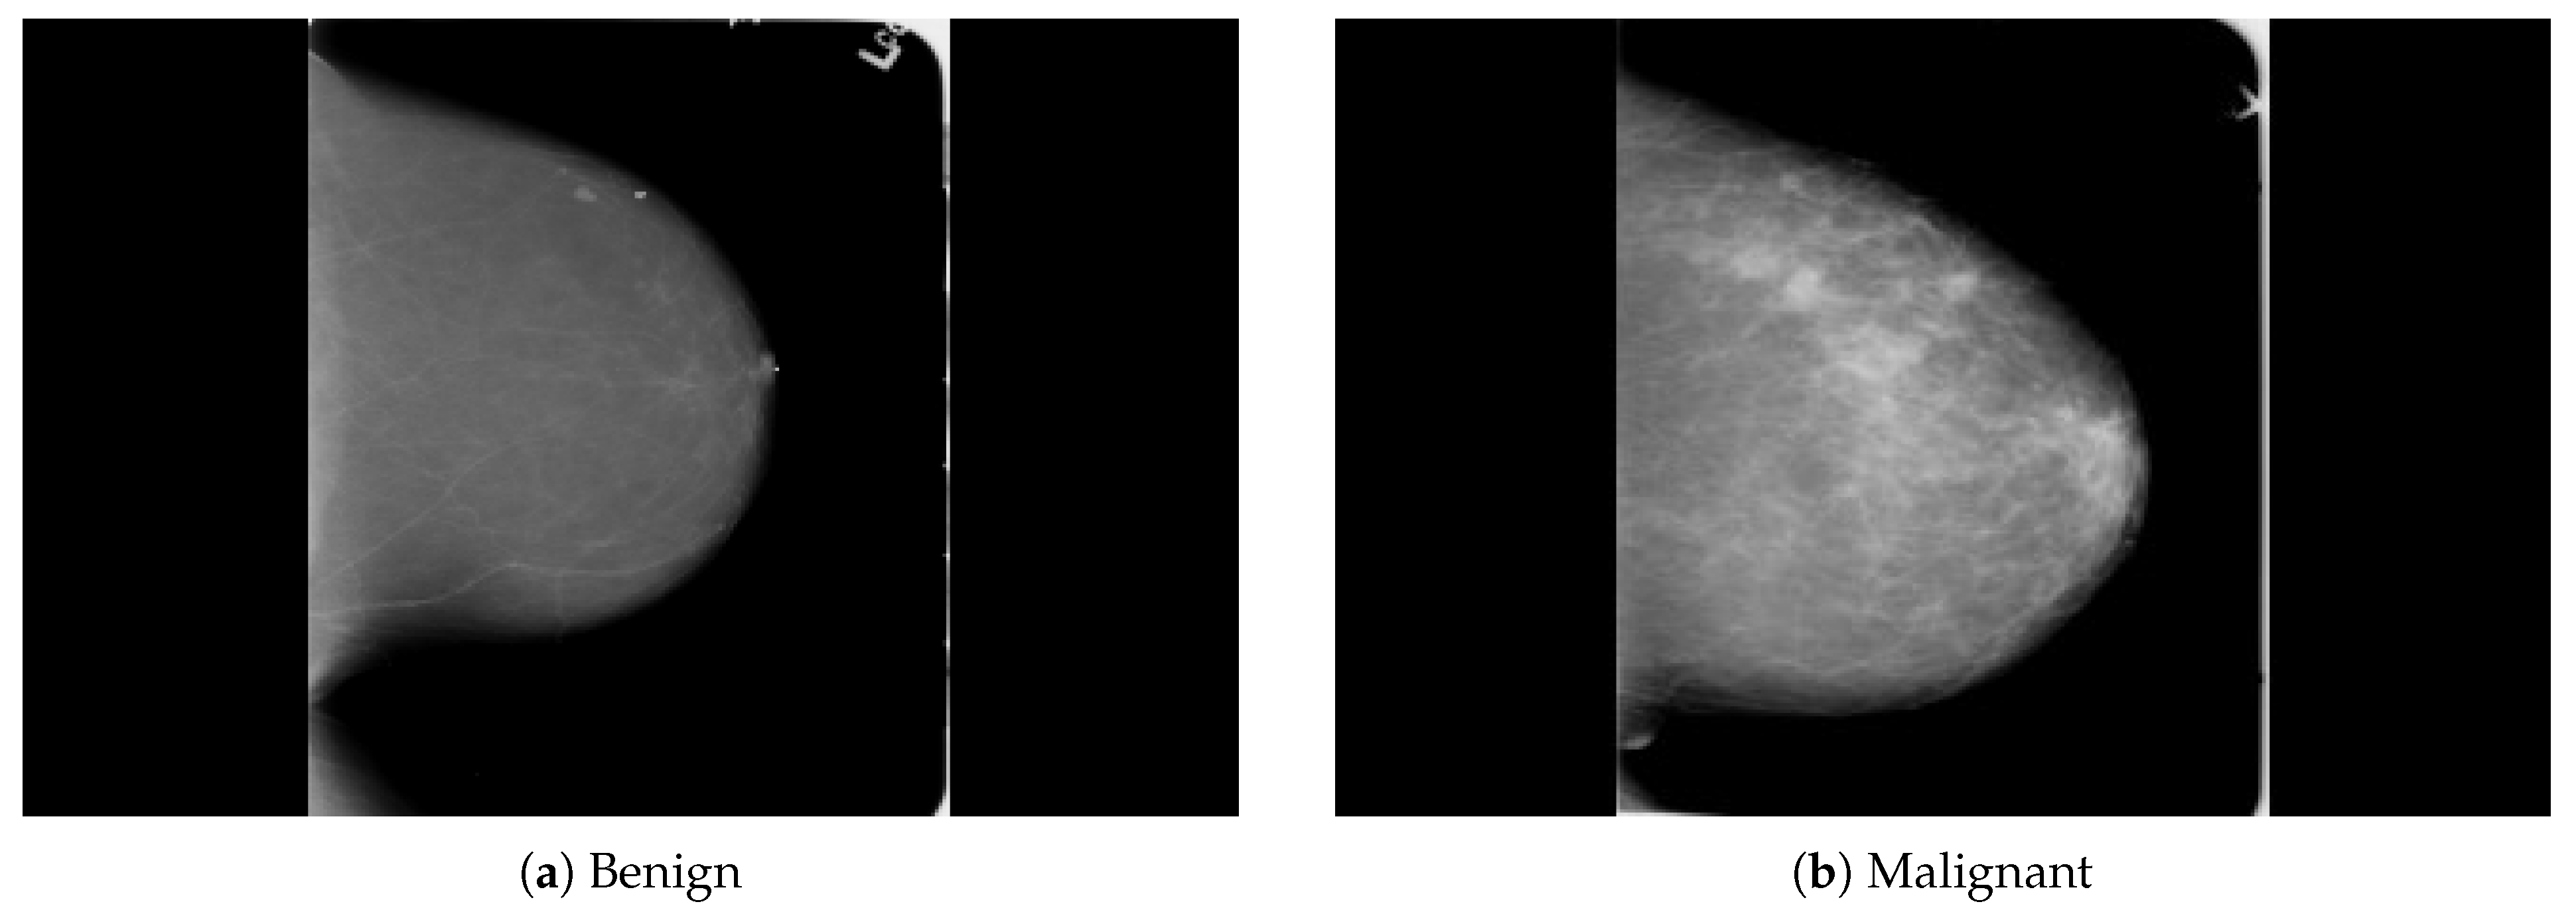

The dataset was collected from a local (PINUM) hospital [51] in Pakistan, with the approval of the Diagnostic Imaging Nuclear Medicine and Radiology Research and Development Committee. A total of 289 patients were manually labeled by the expert radiologist using the initial mammogram reports generated by the mammography machine and included ages between 32 and 73 with a mean age of 48.5 years. The radiologist team consisted of two members, one being a senior radiologist and physicist holding a PhD degree in nuclear medicine with 10 years of experience and the second being a junior radiologist with a Master’s degree in radiology. The dataset was first evaluated with the proposed method to increase the sensitivity of breast cancer prediction using a fully automated CAD system. The dataset included 577 original images consisting of 425 benign and 152 malignant images with both MLO (mediolateral-oblique) and CC (craniocaudal) views at a resolution of 4096 × 2047, as shown in Figure 2. Each CC and MLO view image had a focal length of 35 mm with a 96 dpi resolution along the horizontal and vertical axis. The mammography exam of the PINUM dataset was acquired with Hologic 2D, 3D mammography. Data augmentation techniques were employed on the PINUM dataset to increase the size to regularize and train the deep convolutional neural network. Each mammogram image was rotated at four angles, obtaining five images, including one original and four rotated images. Moreover, we included another public dataset, the Digital Database for Screening Mammography (DDSM) [52], for the evaluation of our model, which contains 3568 mammogram images (1740 benign, 1828 malignant) from 870 benign and 914 malignant cases, as shown in Figure 3. We split the dataset into 60:20:20, where we used 60% for the training of our model, 20% for cross-validation, and the rest for testing. We used 5-fold cross-validation to test our dataset. A detailed description of the dataset is given in Table 1.

Figure 3. An example of breast mammogram images from the DDSM dataset. (a) The benign image. (b) The malignant image. The images were labeled with verified pathology information.